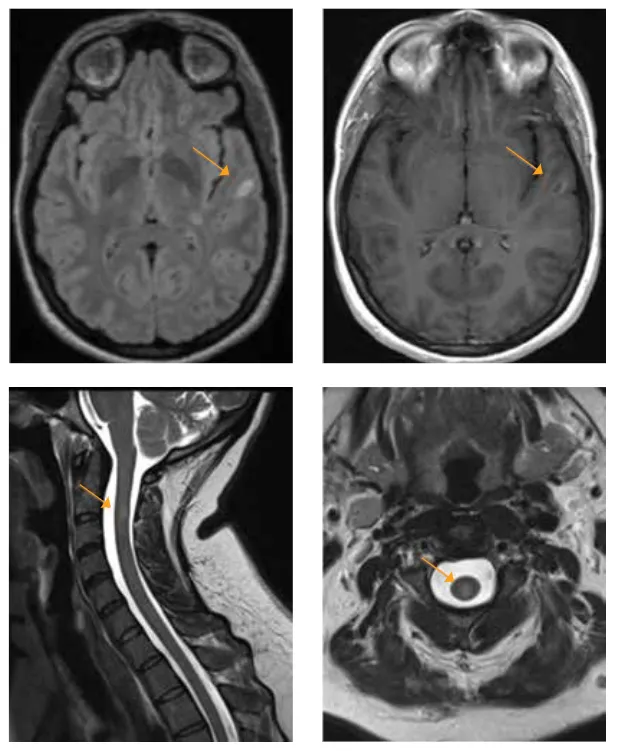

Mizell MS 2

2021 Brain MRI

She had an actively enhancing juxtacortical lesion present in the left temporal region.

In 2021, she began to develop numbness in her right arm and hands that progressed over one month to encompass her left arm and hands. She was seen at AdventHealth Neurology in Winter Park and underwent further testing that included MRI of the brain, cervical and thoracic spine. As her previous images were compared to her current images, she was found to have previous lesions in the brain located in the periventricular and infratentorial region of the brain, which are common locations for lesions of MS.